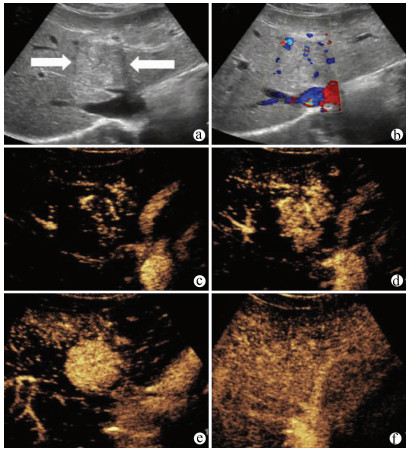

肝病超声诊断指南

中华医学会超声医学分会, 中国研究型医院学会肿瘤介入专业委员会, 国家卫生和健康委员会能力建设和继续教育中心超声医学专家委员会

2021, 37(8): 1770-1785. DOI: 10.3969/j.issn.1001-5256.2021.08.007

摘要(3068) HTML (6587) PDF (9311KB)(804)

超声检查无创、实时、价廉,无辐射、便于反复进行,是最常用的肝脏影像学检查方法。近年来,超声检查新技术如超声造影、弹性成像发展迅速,可有效鉴别肝内占位性病变性质、评估肝纤维化和门静脉高压程度以及监测肝病治疗效果,在临床肝病及其介入治疗中发挥重要诊断价值。本指南规范了肝病多模态超声技术(灰阶超声、彩色多普勒超声、超声造影、弹性超声)检查的仪器调置、患者准备及医生检查方法;对肝脏弥漫性病变(炎性病变、纤维化、硬化)、多种占位性病变及肝病介入操作的多模态超声技术诊断标准进行了定义和规范,同时推荐了超声监测周期及肝脏疾病超声诊断报告书写规范。